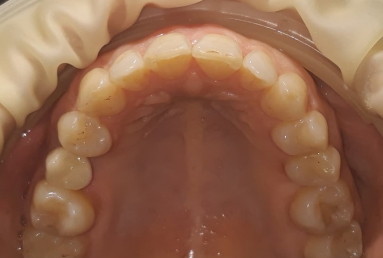

SAPPHIRE ORTHODONTIC DEVICE